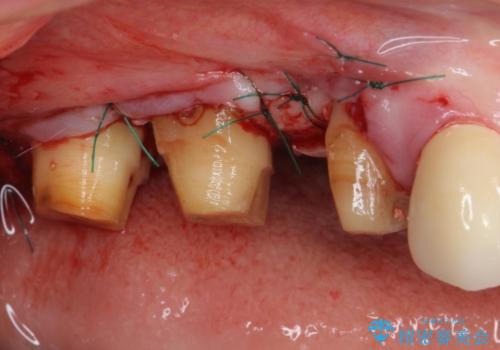

失われていた歯槽骨を、再生治療により可及的に改善させ、その1年後に歯周ポケットを除去するための歯周外科処置を行うこととしました。

処置後はオールセラミックブリッジにて補綴し、再発防止のために就寝時にナイトガード(マウスピース)を装着していただくこととしました。

歯槽骨の再生には1年ほどの待機期間を要し、その後のポケット除去処置も数か月の待機期間を必要とするため、治療期間は長期に及びました。